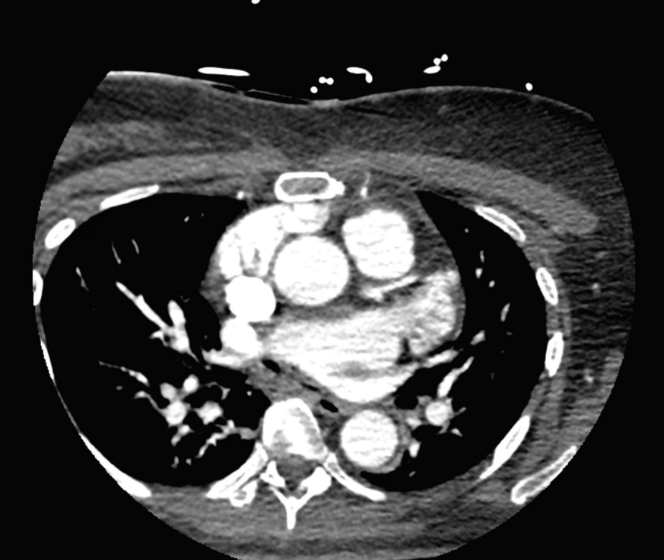

A 57-year-old woman is admitted to the hospital with a fever 2 weeks after a redo-redo atrial fibrillation (AF) ablation using radiofrequency (RF). Her procedure involved focal re-isolation of 2 pulmonary veins (PVs), a left atrial roof line, and posterior wall ablation. Computed tomography (CT) imaging excluded an atrio-esophageal fistula (AEF) and she was treated for post-ablation pericarditis. After a few more weeks of various symptoms, she developed recurrent strokes and sepsis. At that time, she was found to have mediastinal air on a CT scan (Figure) and referred for surgery. In the operating room, a fistula between the esophagus and left main bronchus was taken down and repaired.